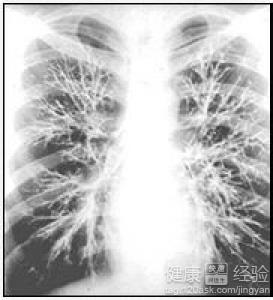

我患有支氣管擴張和肺結核,從去年開始出現濃痰,並帶有血絲現象,在家自己服用了雲南白藥,最近變得更加嚴重,痰中有更多的血,輸液和止血10多天後沒什麼效果,做了支氣管動脈栓塞術。接下來的日子,好了很多,也不咳血了。但是最近這段時間有開始咳出鮮血,我很怕,很苦惱,不知道應該怎麼辦?有沒有什麼有效的方法可以幫幫我呢?

1肺結核是結核桿菌感染引起的疾病,患者會出現咳嗽咳痰甚至咯血等症狀。支氣管炎是由於上呼吸道感染引起的,跟病毒細菌感染都有關系。患者應該注意日常的飲食,多做鍛煉。最好再去醫院檢查。

2建議患者建議住院觀察4、5天。如果沒有鮮紅色血液咳出,說明已經止血。患者會咳出暗紅色的血塊,可能是之前淤積在支氣管的血液,這是正常現象。若沒有異常,可以出院了。

3患者可以采用中醫治療或者西醫治療。如果病情較嚴重,應該先采用西醫治療,等穩定了病情,再采用中醫治療,畢竟中醫的副作用比較小。除了就醫治療,患者還要保持愉悅的心情,注意自己的飲食。